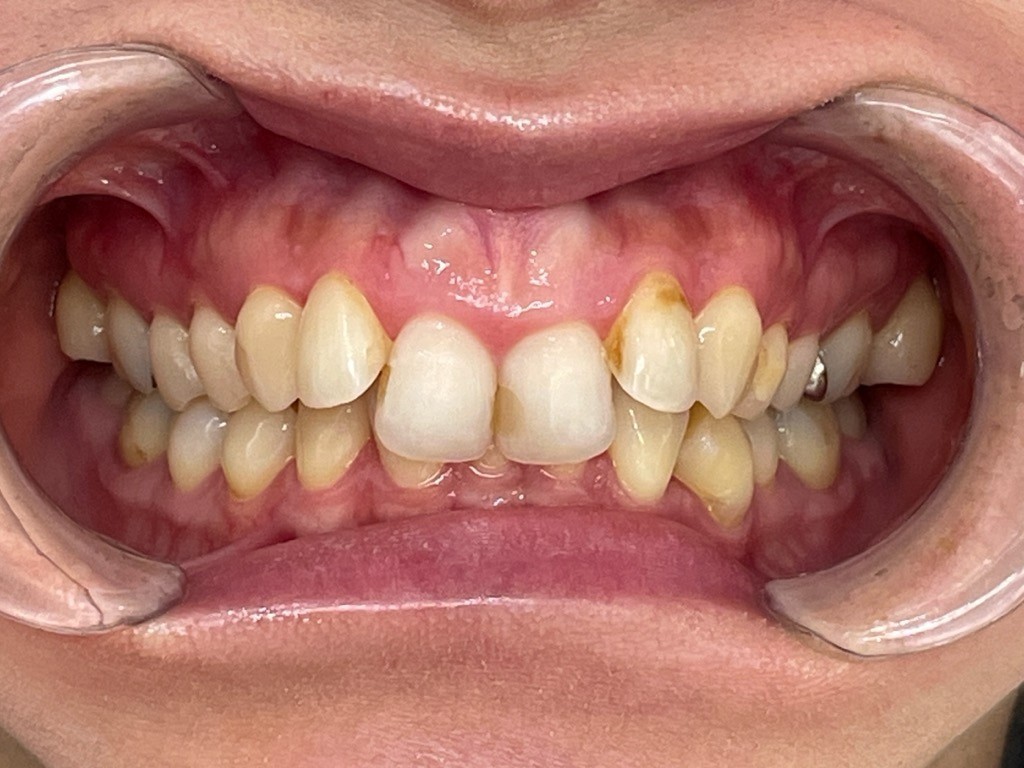

Before

After

矯正の種類 / invisalign GO

年齢・性別 / 10代男性

主訴  /  クロスバイト 嚙み合わせが気になる

治療期間 / 4ヶ月

費用 / 簡易検査 5,000円(税別) 精密検査 30,000円(税別)

両額マウスピース 450,000円(税別)  両額リテイナー料 40,000円(税別)

※マウスピース交換時別途調節料3,000円(税別)

副作用 / 口内炎・歯の移動に伴う痛み・知覚過敏 ※数日で収まる場合が多いです

リスク / 後戻り防止の為、夜のみマウスピースで保定を指示